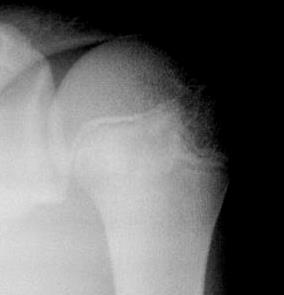

Травма. пациент направлен хирургом в рентгеновский кабинет для рентгенографии плечевого сустава. Были произведены рентгенограммы в двух проекциях. Могу представить, увы, только изображение в прямой проекции.

"Перелом-отрыв бугорка плечевой кости", так любят его наши травматологи, так и называют.

Соглашусь с коллегой Ореховым! Оторвался бугорок!

Ну, и по всей видимости, перелом, без смещения костных отломков.

Насчет линейной тени (две медиальные стрелки) - думаю, не перелом это, закрытая зона роста.

Однозначно, линия, указанная стрелками, это бывшая ростковая зона.

Вот то, что отмечено желтыми стрелочками на последней серии снимков - и есть отрыв большого бугорка. Такой большооооой отрыв большоооооооого бугорка.

Мое мнение, что анатомическая шейка плечевой кости абсолютно интактная! Пациент достаточно молод.